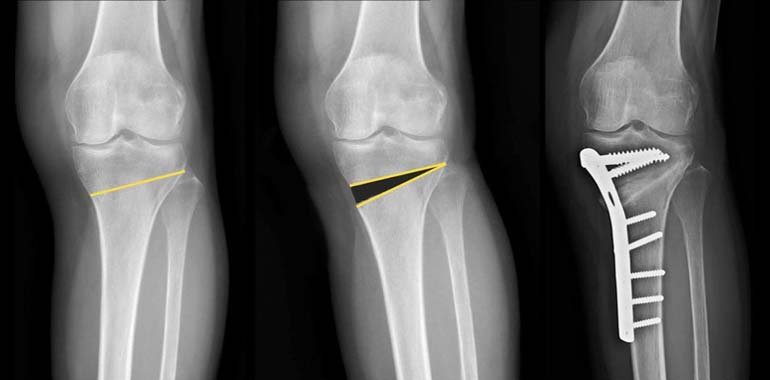

Most osteotomies for knee arthritis are done on the tibia (shinbone) to correct a bowlegged alignment that is putting too much stress on the inside of the knee.

During this procedure, a cut is made on the inside of the tibia, under the unhealthy side of the knee. Using special osteotomes the cut is then opened straightening the leg. This is then fixed with a plate, with or without bone graft.

This procedure is sometimes called a “high tibial osteotomy.”